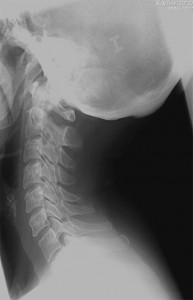

Con el paciente en decúbito prono con la cabeza en posición neutra y los brazos en dirección caudal se coloca el arco de fluoroscopia en posición anteroposterior y se localiza el espacio interlaminar seleccionado con ayuda de un marcador radiopaco. Se debe conseguir que las apófisis espinosas estén equidistantes entre los pedículos y que no exista un doble contorno en los cuerpos vertebrales. Para eliminar el doble contorno si existiera se debe de realizar u movimiento del arco de fluoroscopia en  dirección craneocaudal hasta que desaparezca. No se recomienda la punción en línea media por encima de C5 debido a la elevada incidencia de no fusión del ligamento amarillo. Una vez marcado el lugar de punción se inserta la aguja de Tuohy en visión túnel y dirección al punto diana, la entrada al espacio epidural se realiza  con la técnica de pérdida de resistencia. La técnica se puede realizar con suero, aire y gota pendiente. La elección de la técnica dependerá del entrenamiento de cada profesional con cada una de ellas. Cuando se alcanza el ligamento interespinoso, se rota el arco a posición lateral, para comprobar la profundidda de la aguja y minimizar el riesgo de punción dural. Como la visión lateral a nivel cervical es muy dificultosa por la superposición de las imágenes de los hombros, se utilizan proyecciones oblicuas y en esta posición la punta de la aguja no debe sobrepasar el borde anterior de la apófisis espinosa. Una vez localizado el espacio epidural se inyecta de 1-3ml de contraste radiopaco en tiempo real verificando la posición de la aguja y asegurándonos de que no nos encontramos en el interior de un vaso. Comprobamos nuevamente la distribución del contraste con el arco en posición anteroposterior visualizando el epidurograma y administramos un corticoide no particulado con el anestésico local. Finalmente se retira la aguja con el mandril.